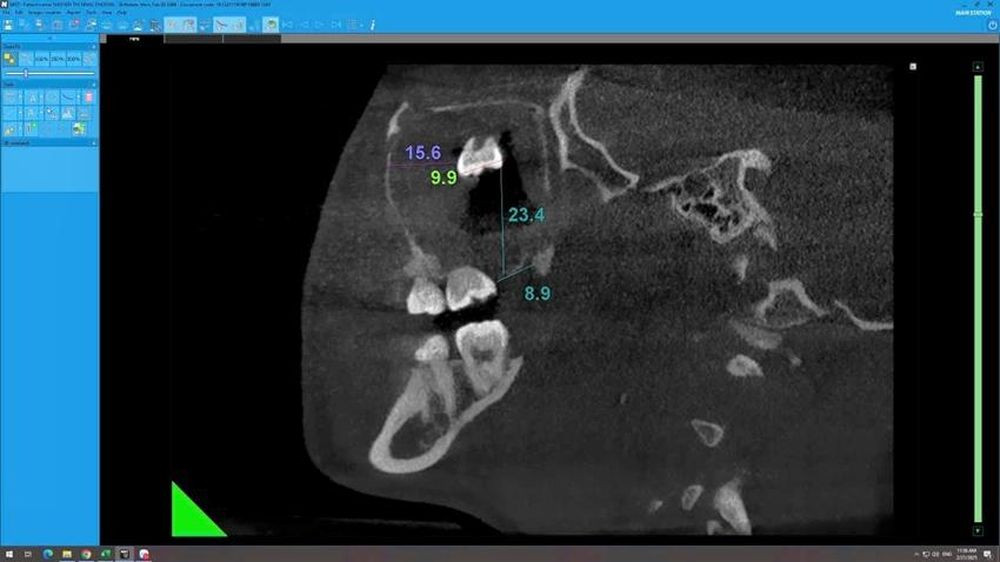

| Răng khôn mọc "lạc chỗ" nằm lâu trong xoang hàm kích thước 6 x 7 x 14 mm qua hình ảnh chụp X-quang. |

Quá trình thực hiện dựa trên hình ảnh đo đạc của hệ thống CT Conebeam Newton hiện đại cho hình ảnh ba chiều rõ nét các phần ở cấu trúc xương hàm. Từ đó, các bác sĩ chẩn đoán chính xác và đưa ra chỉ định tối ưu nhất.

Đây là ca bệnh khó do răng nằm lâu trong xoang hàm gây viêm xoang mạn tính, thoái hóa polyp, răng kích thước lớn (6 x 7 x 14 mm) không thể lấy qua lỗ thông tự nhiên. Các bác sĩ đã hội chẩn, đưa ra quy trình phẫu thuật bài bản, ứng dụng các kỹ thuật mới, ít xâm lấn. Sau đó, ca mổ đã diễn ra thành công, răng ngầm cùng tổ chức bao răng được lấy ra an toàn. Sau can thiệp phẫu thuật, sức khỏe nữ bệnh nhân N.T.N. P. tiến triển tốt.